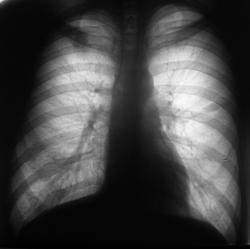

Архив за 2007 год.

Мы посмотрели архив за 2007 год. Сейчас выложу.

Добавлены данные за 2007 год.

Валентин Львович, а тень справа на уровне ключицы и переднего отрезка I ребра (лучше всего видно на снимке за 2007г. - он с небольшим поворотом) это меня глючит?

Я не думаю, что Вас "глючит", так как Вас просто "не может глючить". Я тогда, в 2007 году, "повязал" скиалогическую картину справа на уровне 1 ребра справа, и наличие овальной формы тени средней интенсивности слева в 3 межреберье. Один из наших уважаемых пользователей, сказал как-то, что я "постоянно заточен на туберкулёз", и это правильно, с учетом "нашей эпидситуации". Так вот тогда, я с большим скрипом и неудовольствием, высказался в пользу специфического процесса, хорошо понимая, что данных весьма мало.